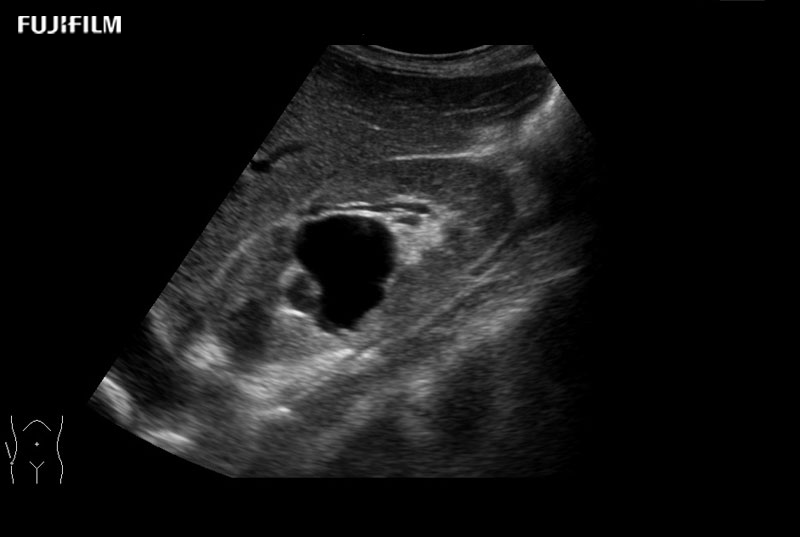

Laparoscopic Cholecystectomy and Hepatectomy using L44LA

Exclusive linear array 4-way laparoscopic transducer for better visualization of targeted lesions.